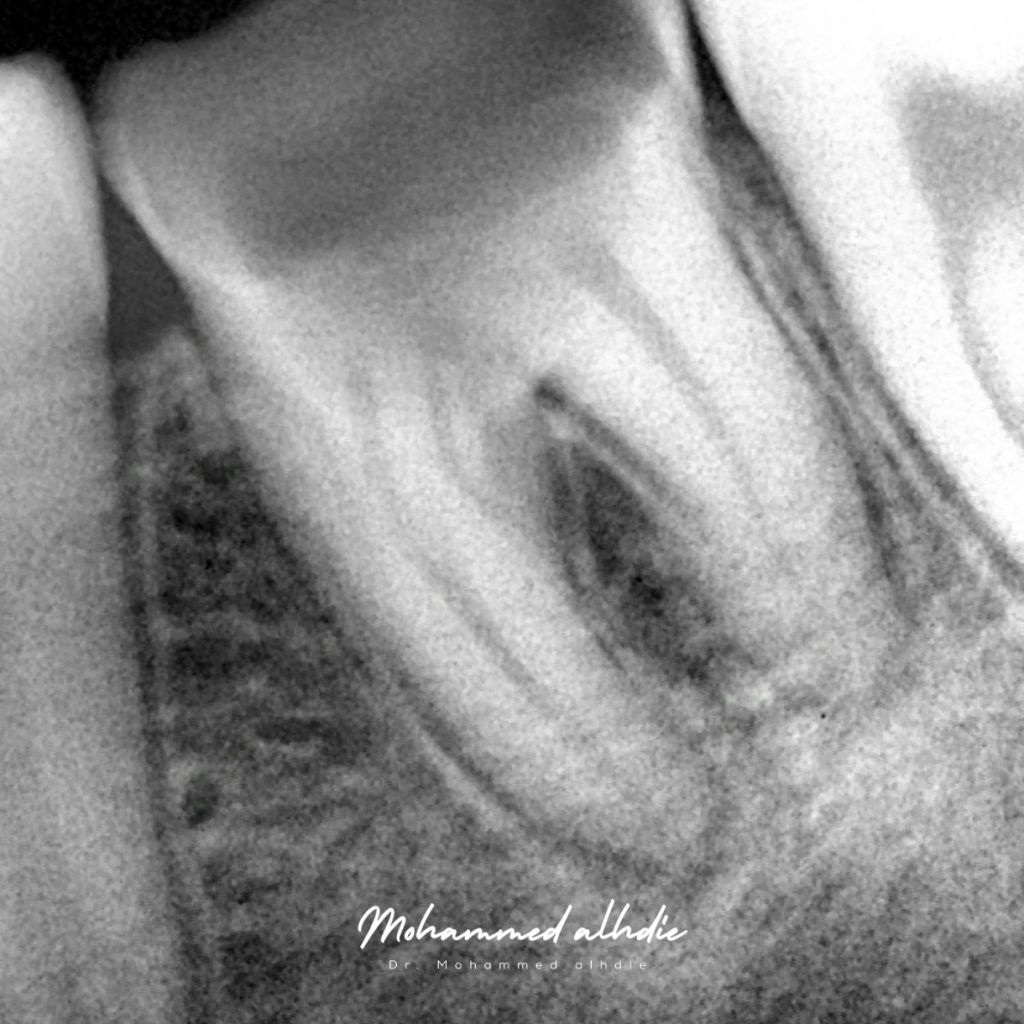

After removing all caries we noticed shadow of redness near to bifurcation area ( this area had thin layer from cementom)

Tp r.c.t and remove thin layer of cementom replaced by bio c putty to increase strength of tooth and finally we did a direct restoration because patient is under 18 in future need overlay or crown